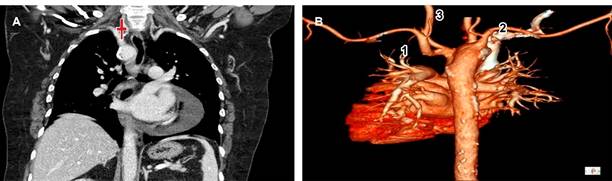

Paciente femenino de 64 años de edad a la que se le solicitó tomografía de tórax en alta resolución por parte del Servicio de Neumología debido a infecciones de vías respiratorias superiores recurrentes; sin embargo, como hallazgo, se visualizó arco aórtico derecho (Figura 1) con patrón de ramificación en espejo (arteria subclavia derecha y arteria carótida común derechos que se originan directamente del cayado aórtico y tronco braquiocefálico izquierdo) (Figura 2).

Figura 2: A) Imagen que muestra corte coronal de angiotomografía de aorta en fase arterial en la cual se observa arteria carótida común derecha (). B) Reconstrucción tridimensional en donde se visualizan tronco braquiocefálico izquierdo (1), arteria subclavia (2) y arteria carótida común derechas (3), compatibles con patrón en espejo.

El tipo I o con patrón de ramificación en espejo es la variación en este caso y representa la categoría más frecuente, consiste en la presencia de un tronco braquiocefálico del lado izquierdo de donde emergen la arteria carótida común y subclavia izquierdas, además de arteria carótida común y subclavia derechas que emergen directamente del arco aórtico y no del tronco braquiocefálico (Figura 2) como ocurre en condiciones normales.1